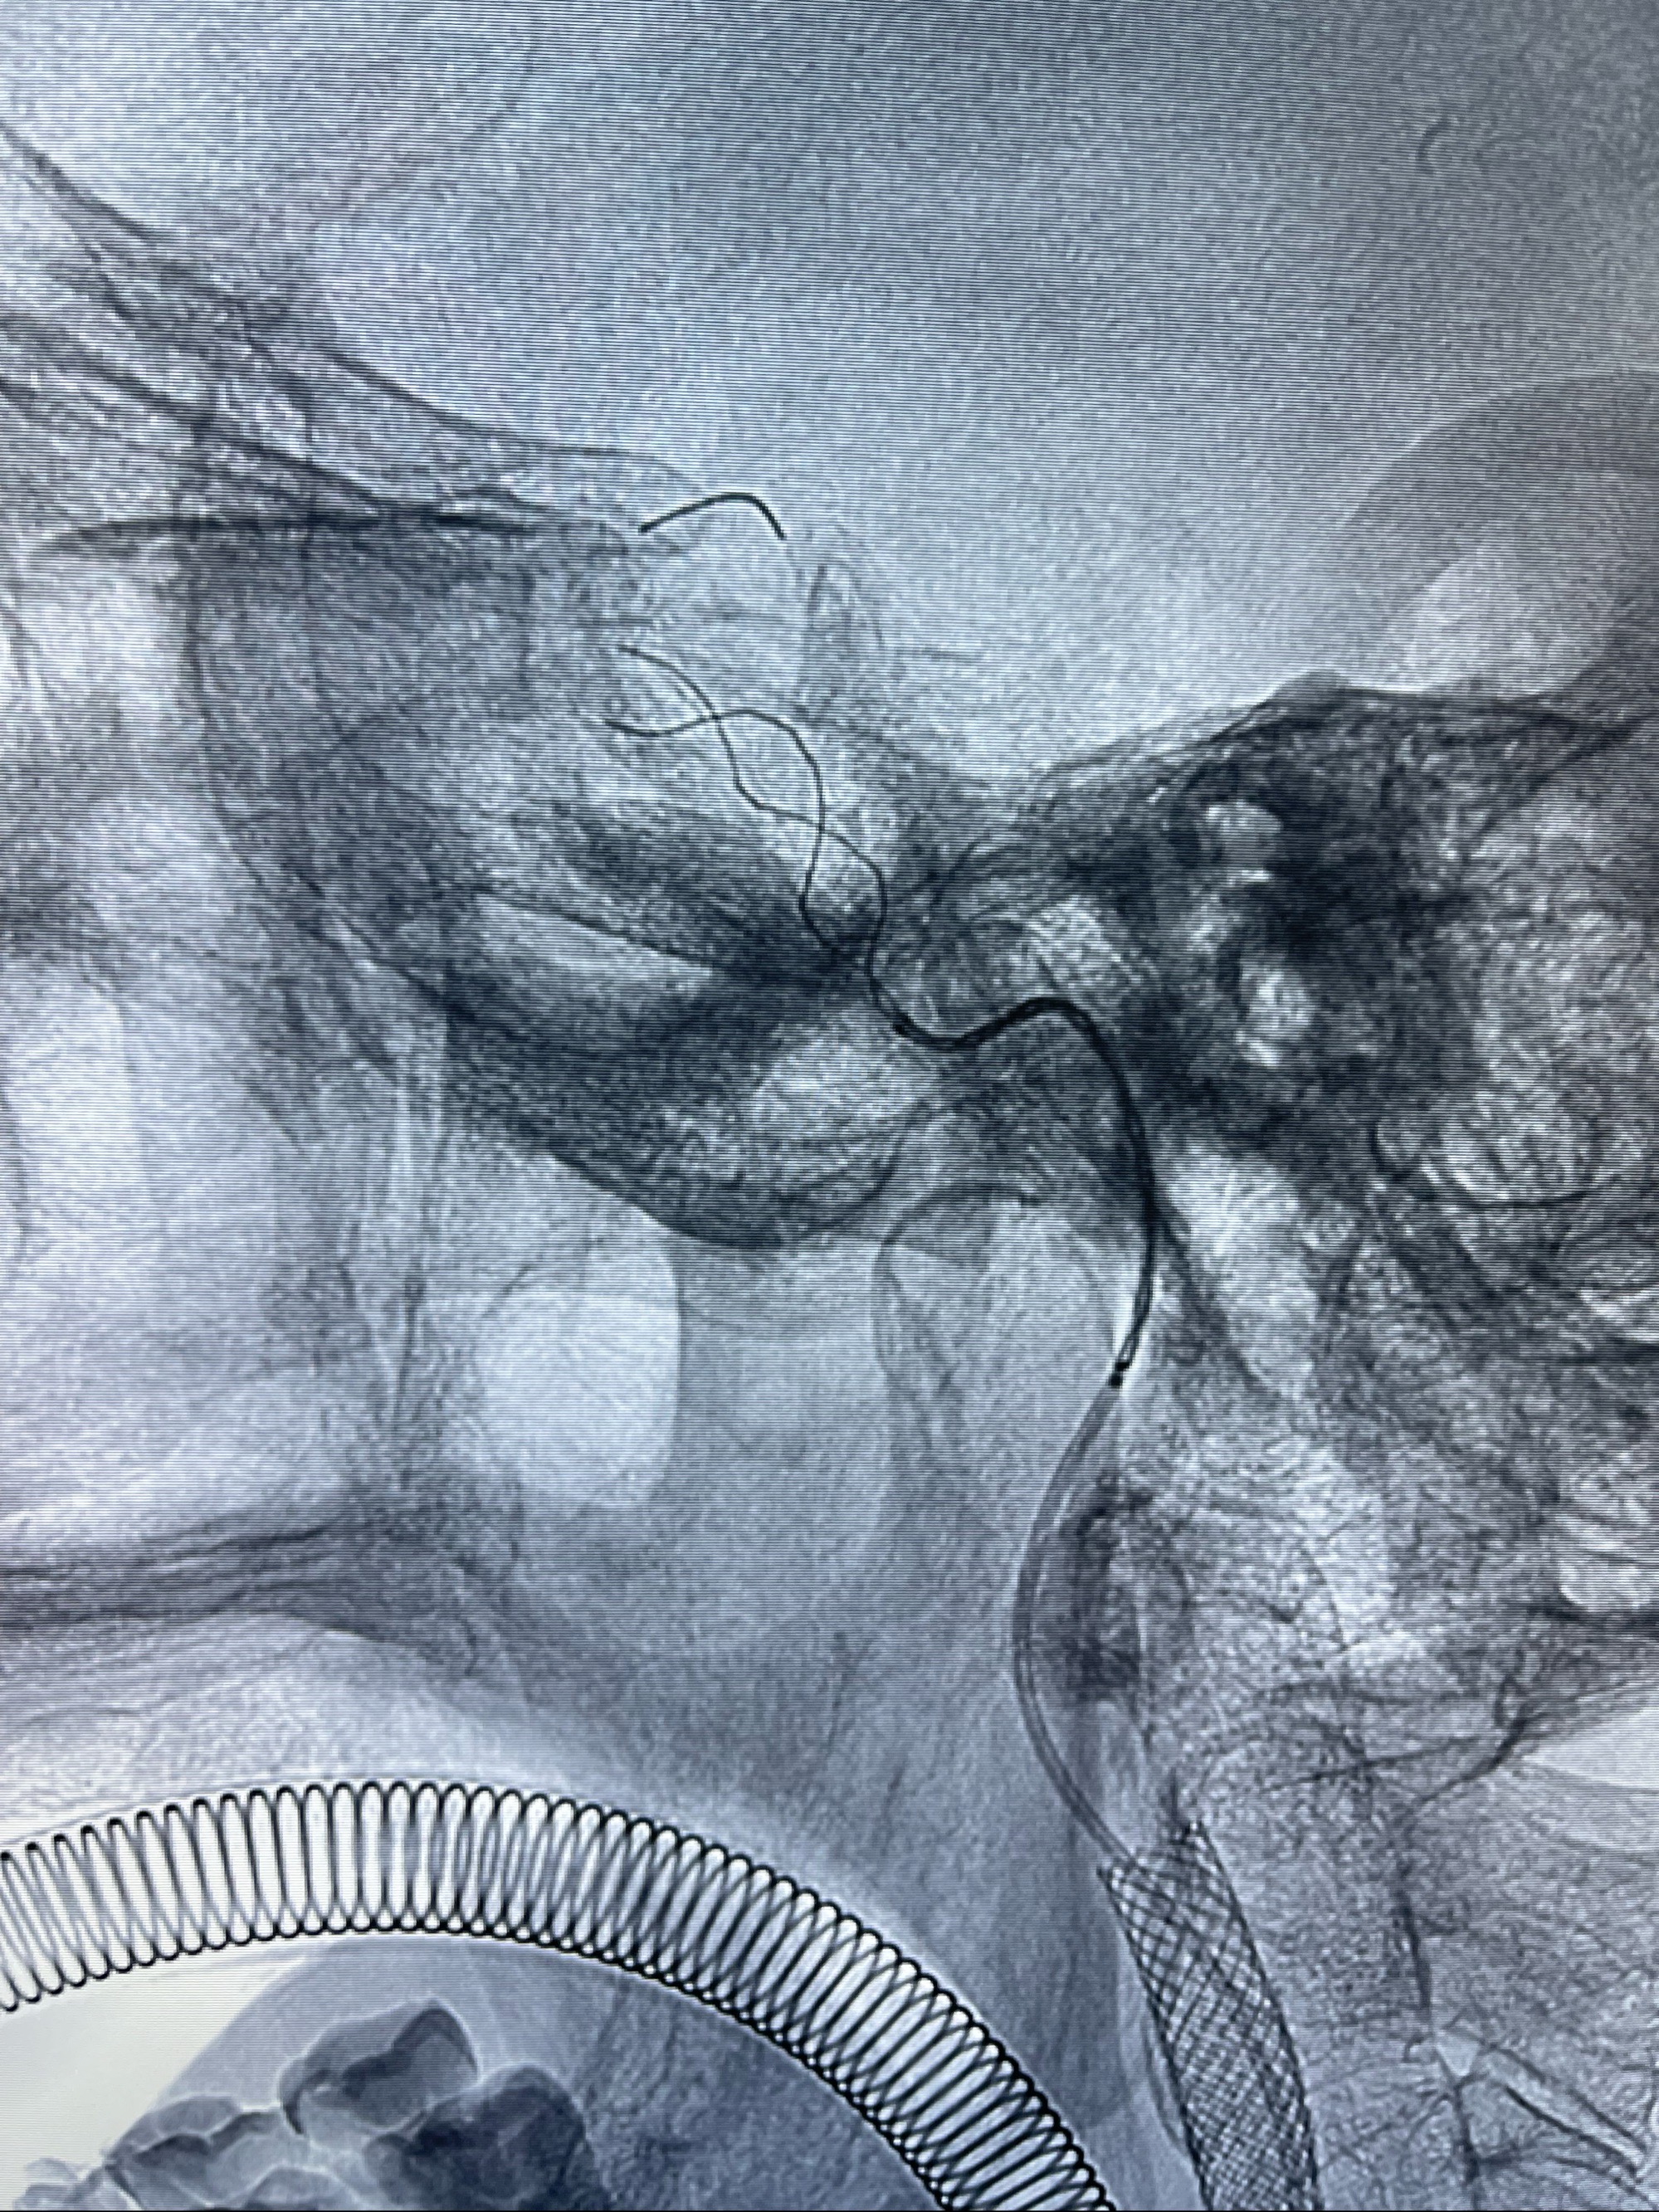

2023-07-10DSA:右侧颈内动脉岩骨段夹层伴中偏重度狭窄改变,左侧颈总动脉闭塞、右侧颈外动脉由右侧肋颈干甲颈干吻合代偿

箭头所示为颈内动脉岩骨段重度狭窄,结合MRI,考虑为肿瘤侵犯右侧颈内动脉

箭头以近至支架段管腔不规则狭窄

088NeuroMAX100cm长鞘在125cmMPA及黑泥鳅导丝引导下超选择性插入右侧颈内动脉支架内

经导引导管造影显示支架远端颈内动脉不规则狭窄伴局部充盈缺损,同时行全身肝素化5ml